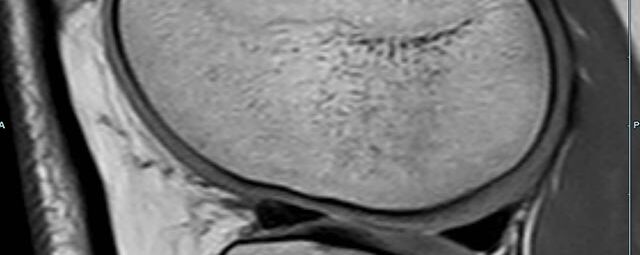

Gelenke

• Beurteilung von Knochen, Bändern und anderen Weichteilstrukturen der Gelenke nach Unfall.

• Arthrosediagnostik (Knorpelschaden)

• Impingement-Symptomatik

• Ursachenklärung bei wiederholter spontaner Gelenkluxation

• Ausbreitungsdiagnostik bei Gelenkentzündung, z.B. im Rahmen von rheumatischen Grunderkrankungen